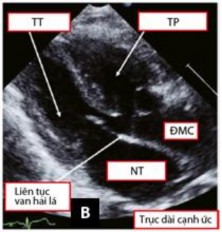

Tiếp theo đó, mặt cắt cạnh ức cao trên trục ngắn cho phép đánh giá tương quan giữa hai đại động mạch và mối liên quan của chúng với lỗ TLT, đánh giá tình trạng của đường ra của các tâm thất (Hình 1.13). Mặt cắt này còn giúp đánh giá xuất phát và đường đi của hai ĐMV. Mặt cắt cạnh ức thấp trên trục ngắn cho phép khảo sát tình trạng của thân và hai nhánh của ĐMP [59],[83].

Hình 1.13: Mặt cắt cạnh ức trong chẩn đoán TPHĐR. (A) Hình ảnh TPHĐR thể chuyển gốc qua mặt cắt cạnh ức trục dài. (B) Mặt cắt cạnh ức trục ngắn cho hình ảnh TPHĐR thể chuyển gốc với ĐMP cưỡi ngựa lên VLT 50% [53]

Mặt cắt cạnh ức trục dài cho phép đánh giá tình trạng liên tục giữa van hai lá - van ĐMC, tương quan và vị trí của hai đại động mạch (Hình 1.14) [84].

Hình 1.14: Hình ảnh TPHĐR thể TLT sử dụng mặt cắt cạnh ức trục dài [34]